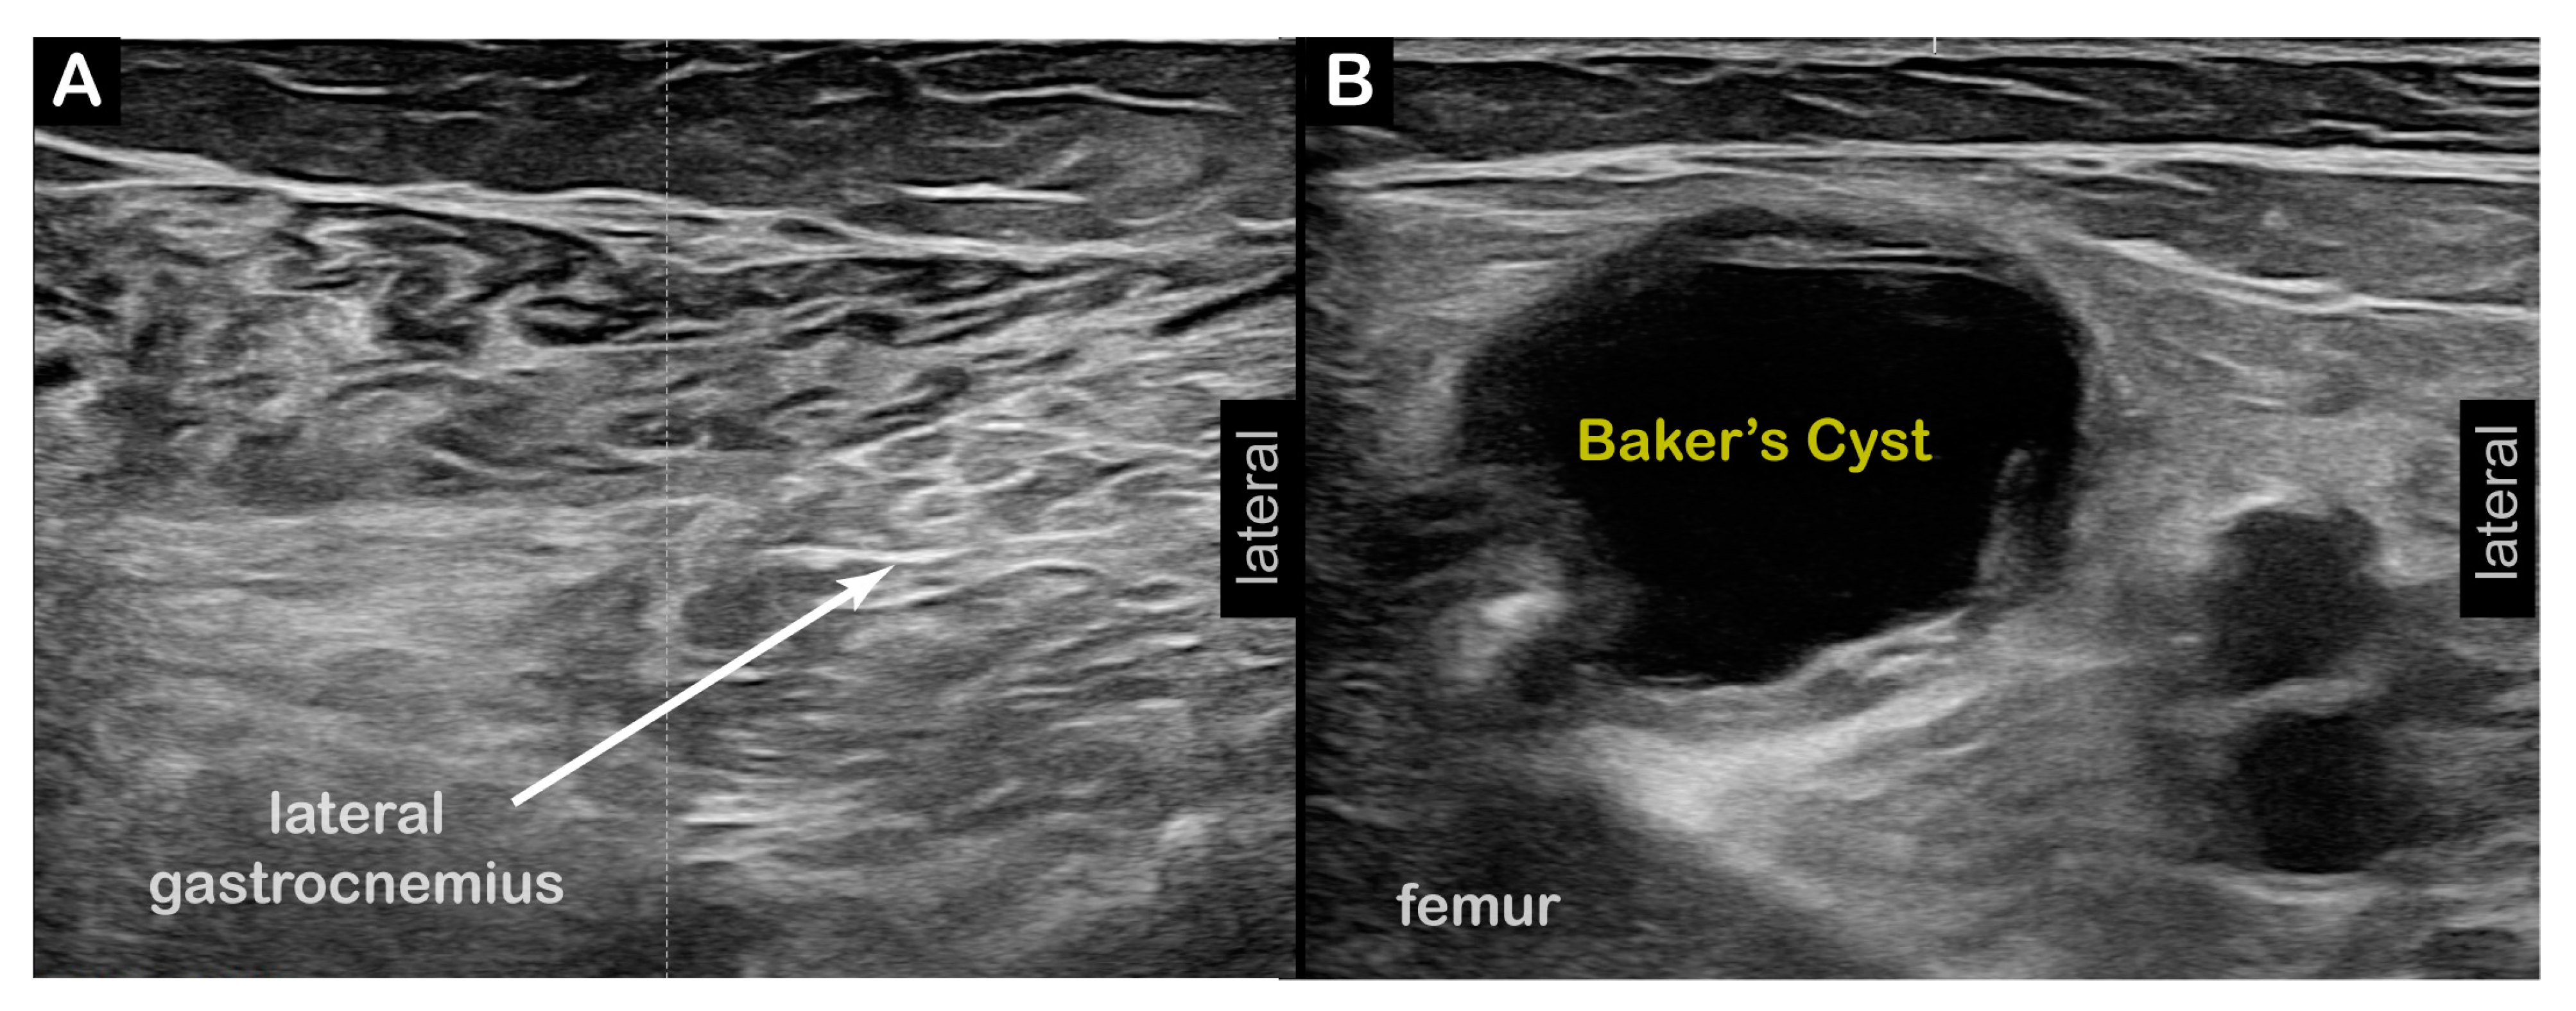

| Diagnostic US |

| Diagnostic US | |